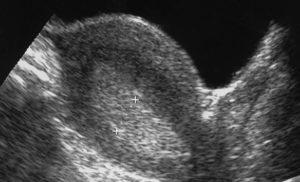

При гиперплазии эндометрия УЗИ проводится с целью изучения изменений, которые произошли в маточной полости, уточнения толщины эндометрия с выявлением очагов патологии и нахождения полипов. Исследование производится специальным датчиком, который вводят женщине во влагалище.

Если при проведении УЗИ выявлено утолщение эндометрия, которое равномерно по значению и оно имеет выраженные контуры, обладая при этом неоднородной эхогенностью, то такие показания являются явным признаком гиперплазии. Кроме того, ультразвуковой метод исследования позволяет выявить наличие полипов.

Такое образование имеет доброкачественный характер и образовывается из тканей эндометрия.

Признаки гиперплазии эндометрия? По УЗИ проявляются его достаточно равномерным утолщением, однородной эхогенностью и ровными контурами. Для полипов характерными признаками являются новообразования, которые имеют повышенную акустическую плотность, ровные контуры и эхонегативный ободок.

Признаки гиперплазии эндометрия по УЗИ: равномерное по значению утолщение с выраженными ровными контурами и однородной эхогенностью.

Эхо-признаками гиперплазии эндометрия являются :

- Утолщение эндометрия (при проведении исследования на 5-7 день цикла показатель м-эха превышает 14,5 мм; в периоде постменопаузы в любой день – более 5 мм)

- Повышение эхогенности

- Изменение рельефа поверхности слизистой оболочки матки

- Изменение (неоднородность) структуры слизистой оболочки матки

- Выявление в пределах эндометрия участков различной формы и размеров с повышенной или пониженной эхогенностью

- Контур М-эха при этом может быть как ровным, так и неровным.